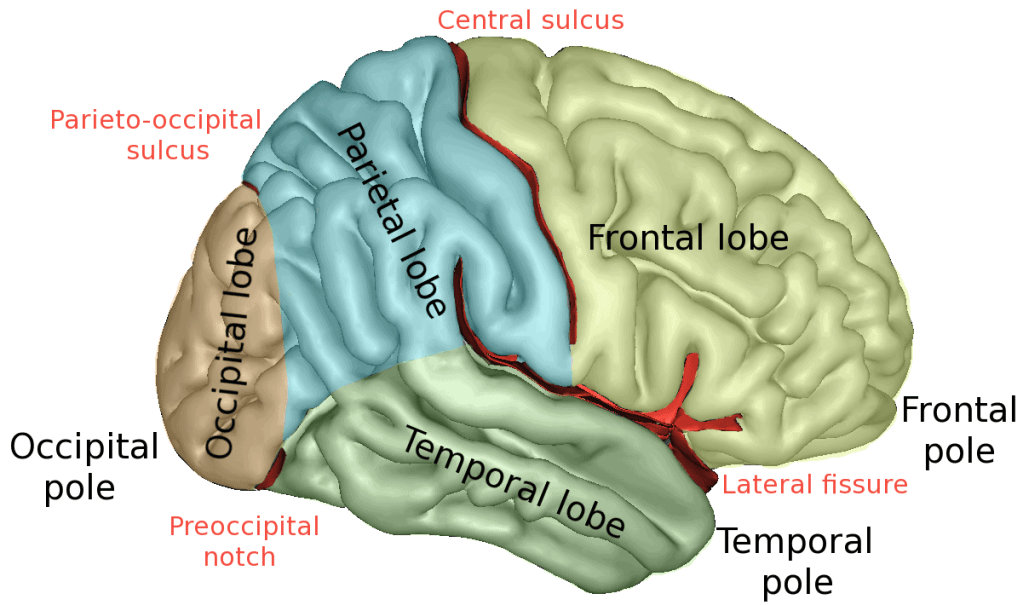

Position and anatomy of the parietal lobe

顶叶的位置和解剖

The parietal lobe is the middle part of the brain. It is located behind the central furrow towards the back. It is separated by incision preoccipitalis from the occipital lobe, lying completely posteriorly (1).

顶叶是大脑的中间部分,它位于背面中央犁沟的后面。

The incisura preoccipitalis cuts into the upper convexity of the brain hemispheres. As a result, the gyrus postcentralis, in which there are sensory centers, belongs to the parietal lobe. There are two curves in the lower area of the parietal lobes. Those are the anterior, gyrus supramarginalis and posterior, gyrus angularis.

枕前切口切入大脑半球的上凸部。因此,感觉中枢的中央后回属于顶叶。顶叶下部有两条曲线。它们分别是前、边缘上回和后、角回。

As already said, the parietal lobe occupies the upper side of the hemisphere. The parietal lobe limits from the anterior and lateral sides include the area from the front to the central sulcus, from the temporal floor to the lateral sulcus, from the occipital sulcus to the imaginary line that flows from the upper edge of the parietal occipital sulcus to the lower hemisphere edge.

如前所述,顶叶位于大脑半球的上半部。从前侧和外侧的顶叶界限包括从前面到中央沟、从颞底到外侧沟、从枕骨沟到从顶枕沟上缘到下半球边缘的假想线。

Parietal lobe syndrome implies an outbreak of function of this lobe due to damage to its structures. This lobe is located between the frontal lobes in both cerebral hemispheres. The parietal lobe extends from the central sulcus to the parieto-occipital groove separating it from the occipital lobe. It contains the primary somatosensory cortex.

顶叶综合征提示该脑叶由于结构损伤而发生功能性疾病。该脑叶位于两个大脑半球的额叶之间。顶叶从中央沟延伸至顶枕沟,将顶叶与枕叶分开。它包含初级躯体感觉皮层。